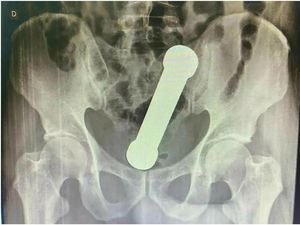

Bikin Ngilu, Barbel 2 Kg Nyangkut di Anus Pria Ini! Kok Bisa?

Seorang pria di Brasil terpaksa dioperasi untuk mengeluarkan barbel seberat 2 kg dari dalam anusnya. Barbel itu tersangkut setelah dimasukkan demi kepuasan seks